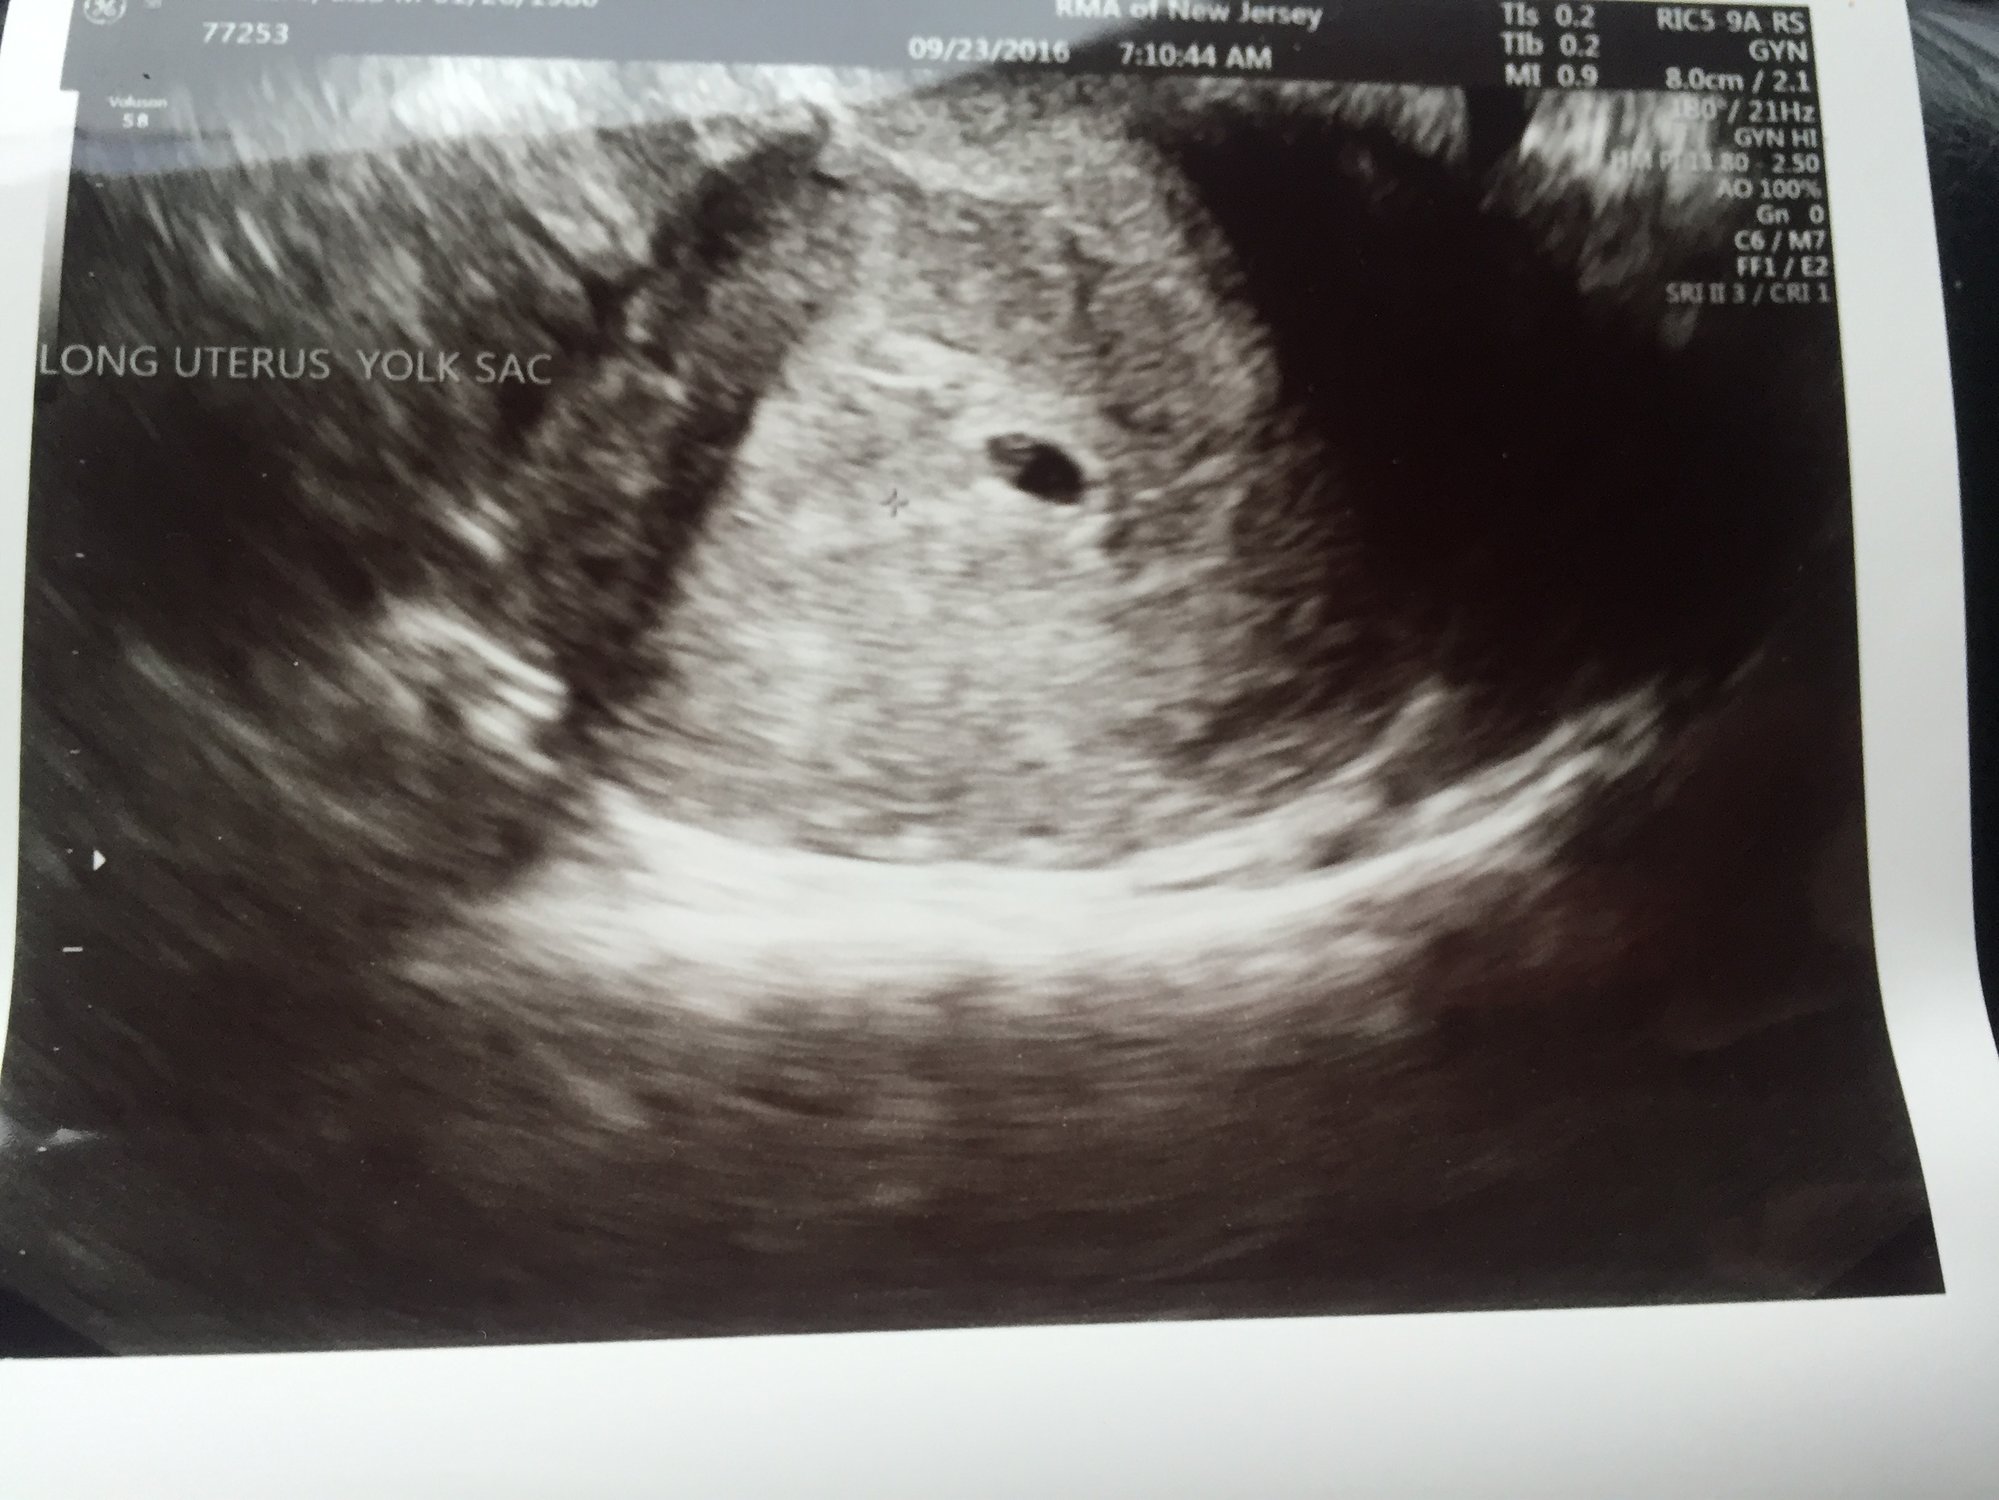

Well my name is Lisa, from Manalapan Nj (although I'm still a Bklyn girl at heart). Had a long hard time conceiving. Long story short having a kid on our own can never happen. We had our FET 9.6.16. We put 2 healthy PGS tested embryos. My first beta 9dpt were not really that high but have been more than doubling now. We will have our first US on Friday which will be 5wks 1day. Doubt we will see much but as long as my levels are even higher and he says everything looks good, that's all we need to hear! Congrats to all and wishing you all a H n H 9 months! We will be due 5/25/17.

Married my best friend in 2013 (I was 33), After 1.5yrs of TTC got my first BFP naturally on 2/7/15 but ended in DNC on 4/14/15, not viable. In 2015 I was 35...Found out I had only one working ovary, which was DOR, with scar tissue and I ovulated at 7 days, with a small cervix opening and a tilted uterus... Needing an RE was a must.....IUI#1 Sept 2015,,, BFN IUI#2 Oct 2015,,,BFN IUI#3 Dec 2015,,BFN IVF#1 2/1/16- BFN IVF# on 3/29/16 retrieval only - 1 healthy chromosome tested embryo. IVF#3 retrieval 4/23/16- 0 healthy embryos. IVF#4 retrieval 6/17/16- 1 healthy embryo. FET#1-Transferred Both Healthy Embryos on 9/6/16 BFP!! 9/15/16 Beta 22.3, 9/17/16 Beta 60.5 & 9/19/16 Beta 195! 1st US on 9/23/16, only 1 Gast Sac & Yolk Sac found, US 9/30/16 US 6wk 1day saw and heard Heartbeat 120bpm!! EDD 5/25/2017 Had a healthy baby girl via CSection on 5/18/17 8lbs 15oz. Then four months later got pregnant naturally and had a healthy baby boy on 6/13/18 7lbs 6oz (at age 38). Needless to say, anything is possible! I'm keeping my signature open so it gives someone out there hope that anything is possible. Message me if you ever have any questions or just need someone to talk to. DON'T GIVE UP!

Well today we went in for our 5wk 1d US. All is looking good. Better than what the dr thought it would be. Gas Sac and Yolk sac and even a small fetal pole. We will be waiting another week to hear the heartbeat.

*****Trigger Warning, Loss and Pregnancy Mentioned*****